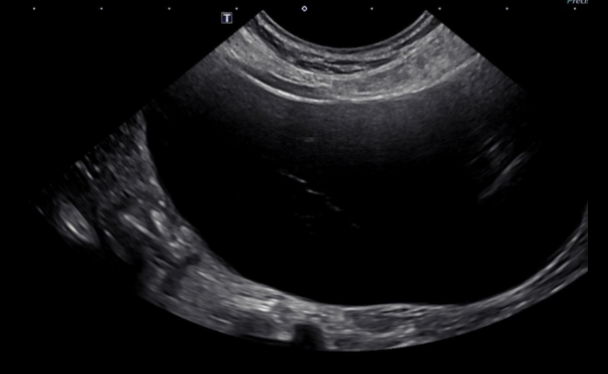

Curvilinear

Pie shaped image

Useful in areas that are deeper

Variable frequencies and size

E.g standard sized dogs

Less detail